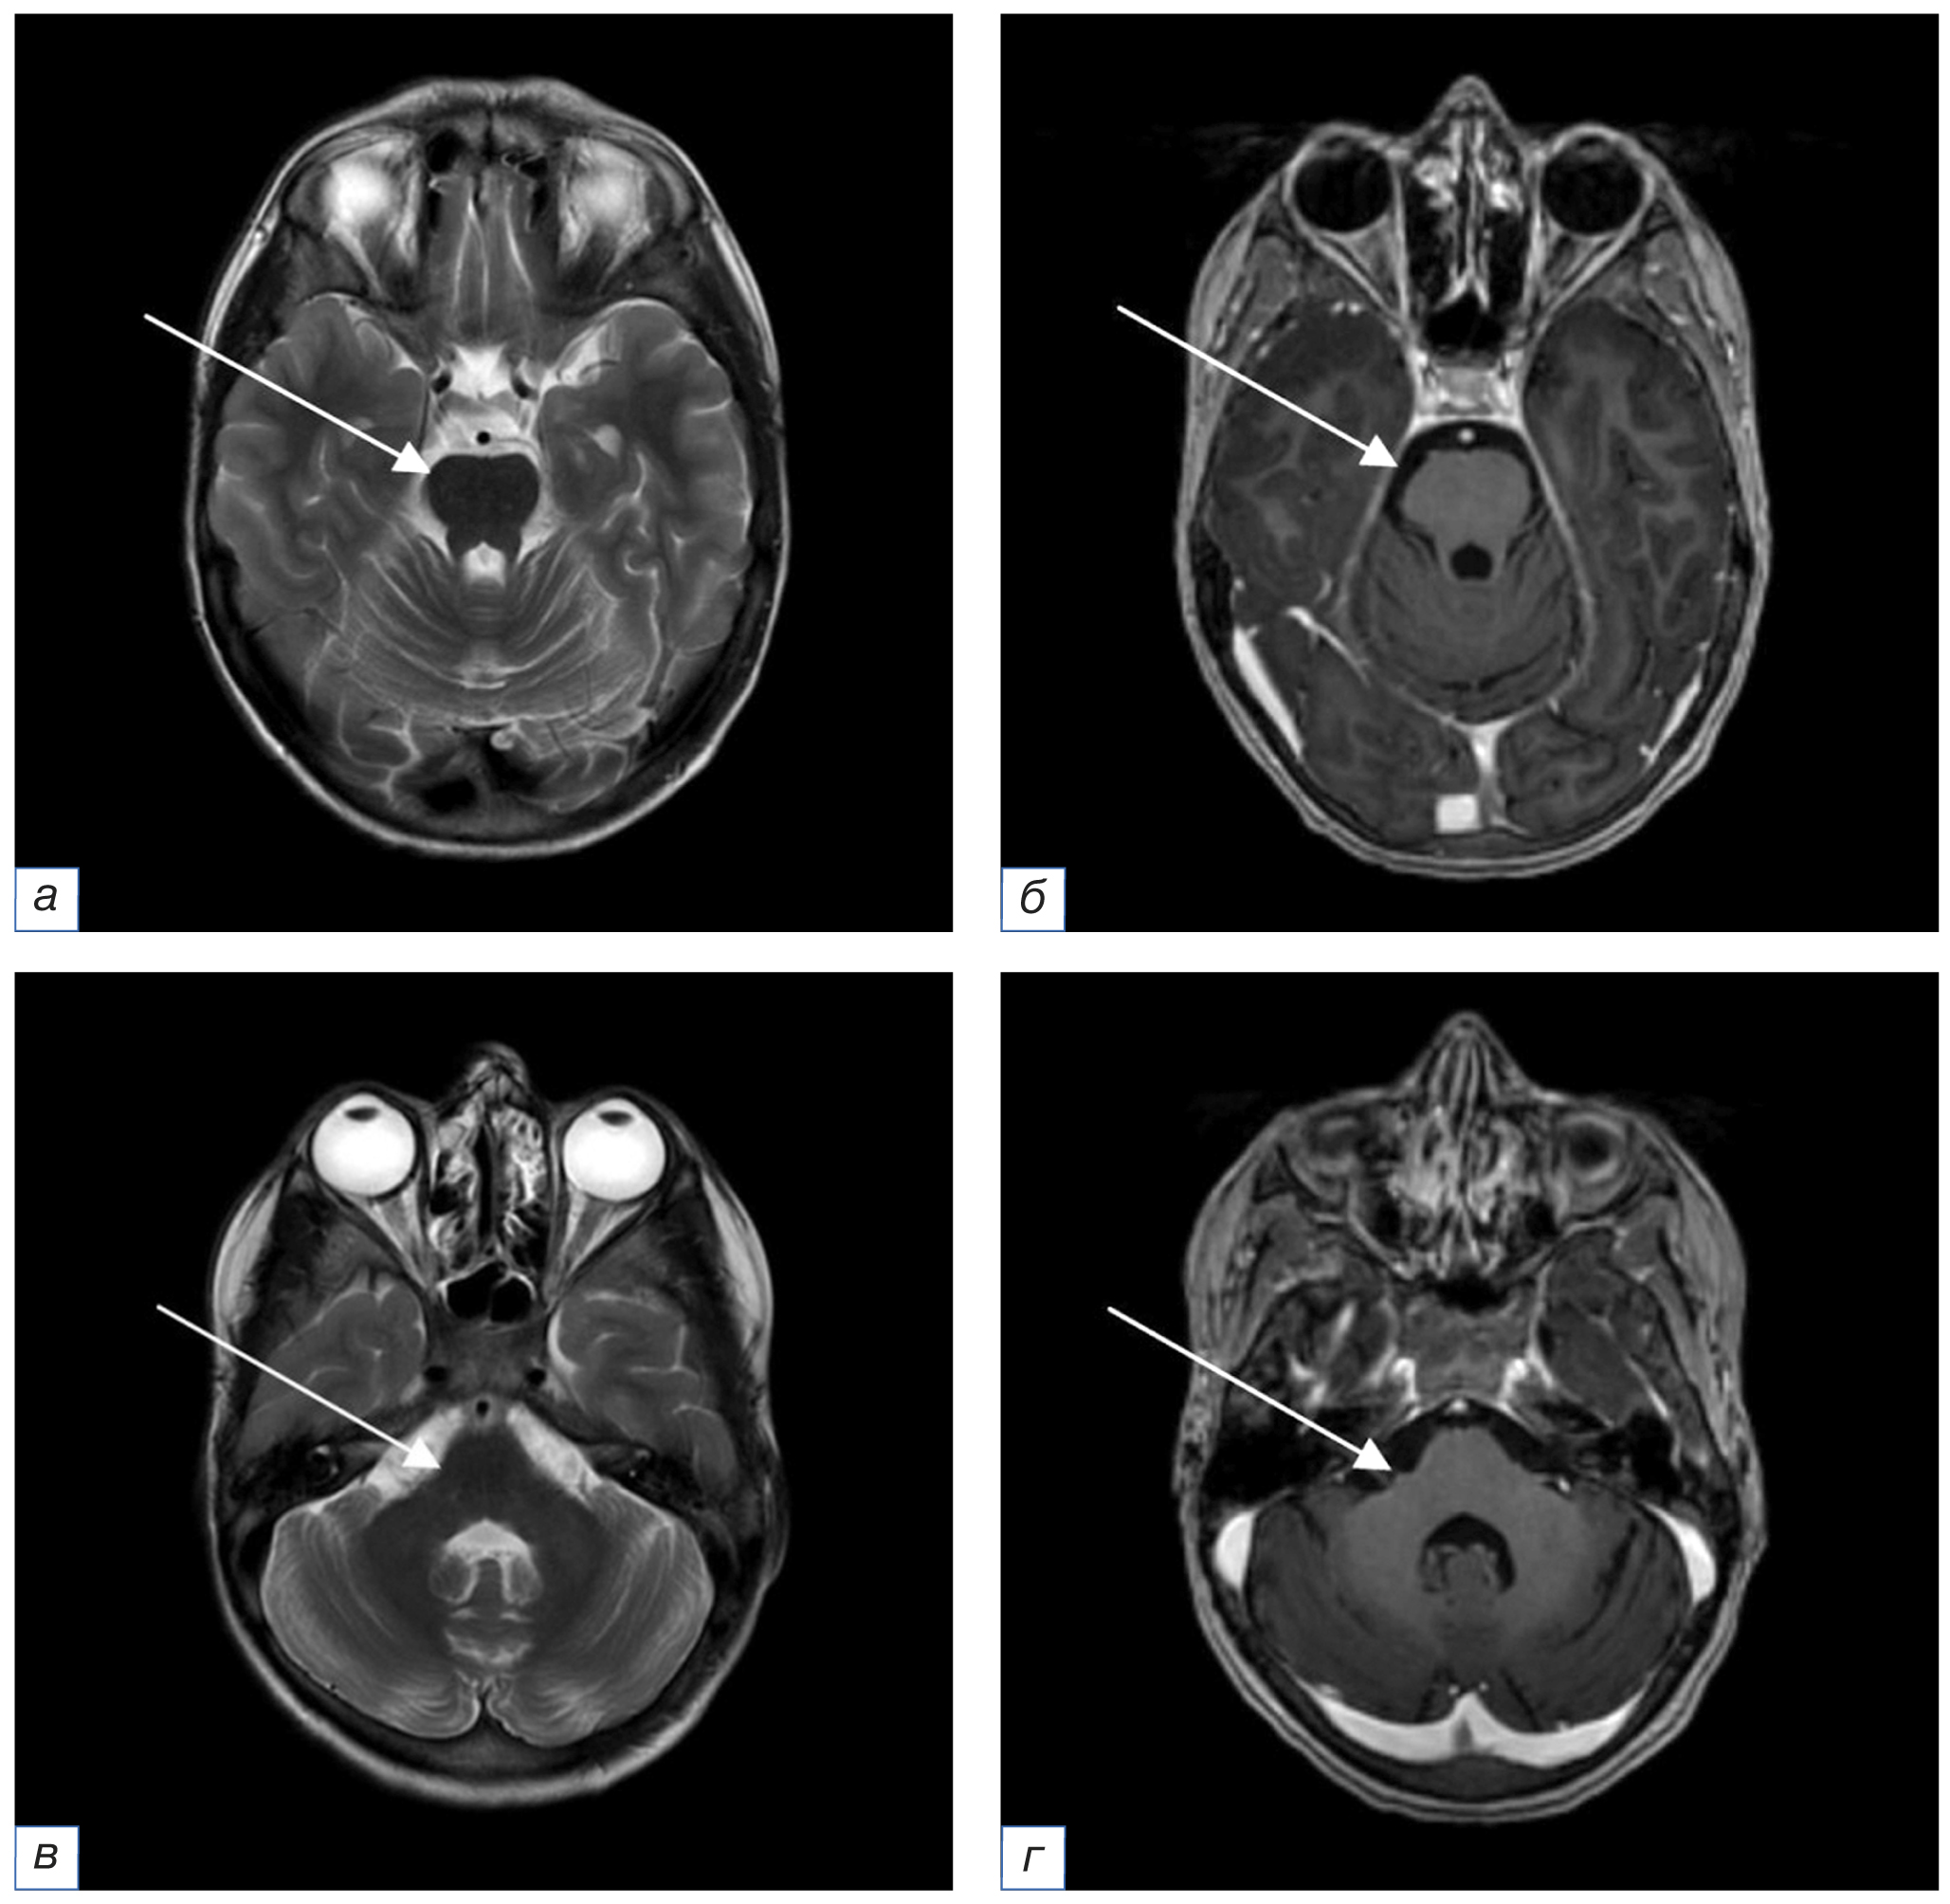

18.03.2022 (через 16 дней после пульс-терапии Метипредом) отмечалось ухудшение состояния ребенка в виде нарастания атаксии. МРТ головного мозга с контрастным усилением от 25.03.2022 (рис. 4) выявило отрицательную динамику: увеличение количества очагов измененного МР-сигнала. МРТ спинного мозга с контрастным усилением патологии не выявило. С целью исключения васкулита центральной нервной системы ребенку проведены МР-ангиография и церебральная ангиография: патологии не выявлено. Для купирования обострения основного заболевания проведена пульс-терапия метилпреднизолоном в дозе 750 мг внутривенно капельно. На фоне терапии отмечалась положительная динамика в виде уменьшения степени выраженности клинических проявлений. Далее с профилактической целью назначена терапия метилпреднизолоном в дозе 26 мг/сут перорально.

Рис. 4. МРТ головного мозга с внутривенным контрастным усилением в аксиальной плоскости от 25.03.2022 на фоне клинического обострения (a, в — режим Т2-ВИ; б, г — режим Т1-ВИ после введения контрастного вещества): по сравнению с данными МРТ от 16.08.2021 отмечается отрицательная динамика в виде увеличения размеров и количества очагов с интенсивным накоплением контрастного вещества (стрелки). / Fig. 4. MRI of the brain in the axial plane of March 25, 2022 with intravenous contrast enhancement in the acute stage of CLIPPERS (a, в — T2-weighted image; б, г — T1-weighted image after contrast enhancement): compared with the MRI data of August 16, 2021, a negative trend is observed namely an increase in the size and number of foci with strong contrast enhancement (arrows).

15.06.2022. По данным МРТ головного мозга с контрастным усилением (рис. 5) в сравнении с исследованием от 25.03.2022 отмечается положительная динамика в виде регресса ранее выявленных субтенториальных очагов.

Рис. 5. МРТ головного мозга с внутривенным контрастным усилением в аксиальной плоскости от 15.06.2022 после курса пульс-терапии и поддерживающей терапии кортикостероидами на протяжении 3 мес (a, в, д — режим Т2-ВИ; б, г, е — режим Т1-ВИ после введения контрастного вещества): по сравнению с данными МРТ от 25.03.2022 отмечается регресс очаговых изменений субтенториальных структур (стрелки). Участки патологического накопления контрастного вещества не определяются. / Fig. 5. MRI of the brain in the axial plane of June 15, 2022 with intravenous contrast enhancement after a course of pulse therapy and maintenance therapy with corticosteroids for three months (a, в, д — T2-weighted image; б, г, е — T1-weighted image after contrast enhancement): compared with the MRI data of March 25, 2022 there is a regression of focal changes in the subtentorial structures (arrows). Absence of pathological contrast enhancement.

27.10.2022. По результатам МРТ головного мозга с внутривенным контрастным усилением (рис. 6) на фоне поддерживающей терапии кортикостероидами на протяжении 7 мес не отмечается новых очаговых изменений, участков патологического накопления контрастного вещества не определяется. Однако выявляются сопутствующие вторичные изменения больших полушарий и моста, наиболее вероятно, соответствующие псевдоатрофии в результате уменьшения воспалительного отека на фоне стероидной терапии, с умеренным расширением ликворных пространств.

Рис. 6. МРТ головного мозга с внутривенным контрастным усилением в аксиальной плоскости от 27.10.2022 после поддерживающей терапии кортикостероидами на протяжении 7 мес (a, б — режим Т1-ВИ до и после введения контрастного вещества соответственно; в, д — режим Т2-ВИ; г, е — режим FLAIR): по сравнению с данными МРТ от 15.06.2022 появления новых очаговых изменений не отмечается. Участков патологического накопления контрастного вещества не определяется. Однако визуализируются изменения МР-сигнала в мосту (белые стрелки) и уменьшение объёма белого вещества больших полушарий с вторичным расширением ликворных пространств (красные стрелки), вероятно, как проявление псевдоатрофии на фоне стероидной терапии. / Fig. 6. MRI of the brain in the axial plane of October 27, 2022 with intravenous contrast enhancement after a maintenance therapy with corticosteroids for seven months (a, б — T1-weighted image before and after contrast enhancement respectively; в, д — T2-weighted image; г, е — FLAIR): compared with the MRI data of June 15, 2022 no new focal changes have appeared. Absence of pathological contrast enhancement. However there are changes of the MR signal in the pons (white arrows) and changes of the white matter of the brain hemispheres with secondary dilatation of liquor spaces (red arrows) specific to pseudoatrophy during the treatment with steroids.